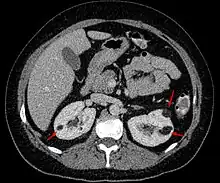

| Angiomyolipoma in both kidneys (arrows) in computer tomography. The tumours are hypodense (dark) due to fat content. | |

Three methods of scanning can detect angiomyolipomas: ultrasound, computed tomography (CT), and magnetic resonance imaging (MRI).[5] Ultrasound is standard and is particularly sensitive to the fat in angiomyolipomas, but less so to the solid components. However, accurate measurements are hard to make with ultrasound, particularly if the angiomyolipoma is near the surface of the kidney (grade III).[4] CT is very detailed and fast, and allows accurate measurement. However, it exposes the patient to radiation and the dangers that a contrast dye used to aid the scanning may itself harm the kidneys. MRI is safer than CT, but many patients (particularly those with the learning difficulties or behavioural problems found in tuberous sclerosis) require sedation or general anaesthesia, and the scan cannot be performed quickly.[3] Some other kidney tumours contain fat, so the presence of fat is not diagnostic. Distinguishing a fat-poor angiomyolipoma from a renal cell carcinoma (RCC) can be difficult.[6] Both minimal fat AMLs and 80% of the clear-cell type of RCCs display signal drop on an out-of-phase MRI sequence compared to in-phase.[7] Thus, a lesion growing at greater than 5 mm per year may warrant a biopsy for diagnosis.[3]